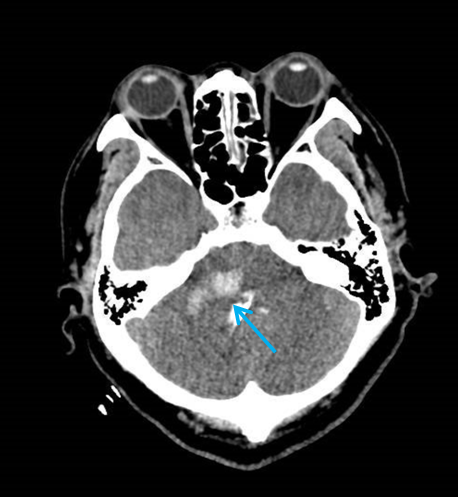

术后颅脑CT可见脑干血肿清除(蓝色箭头所示为引流管)